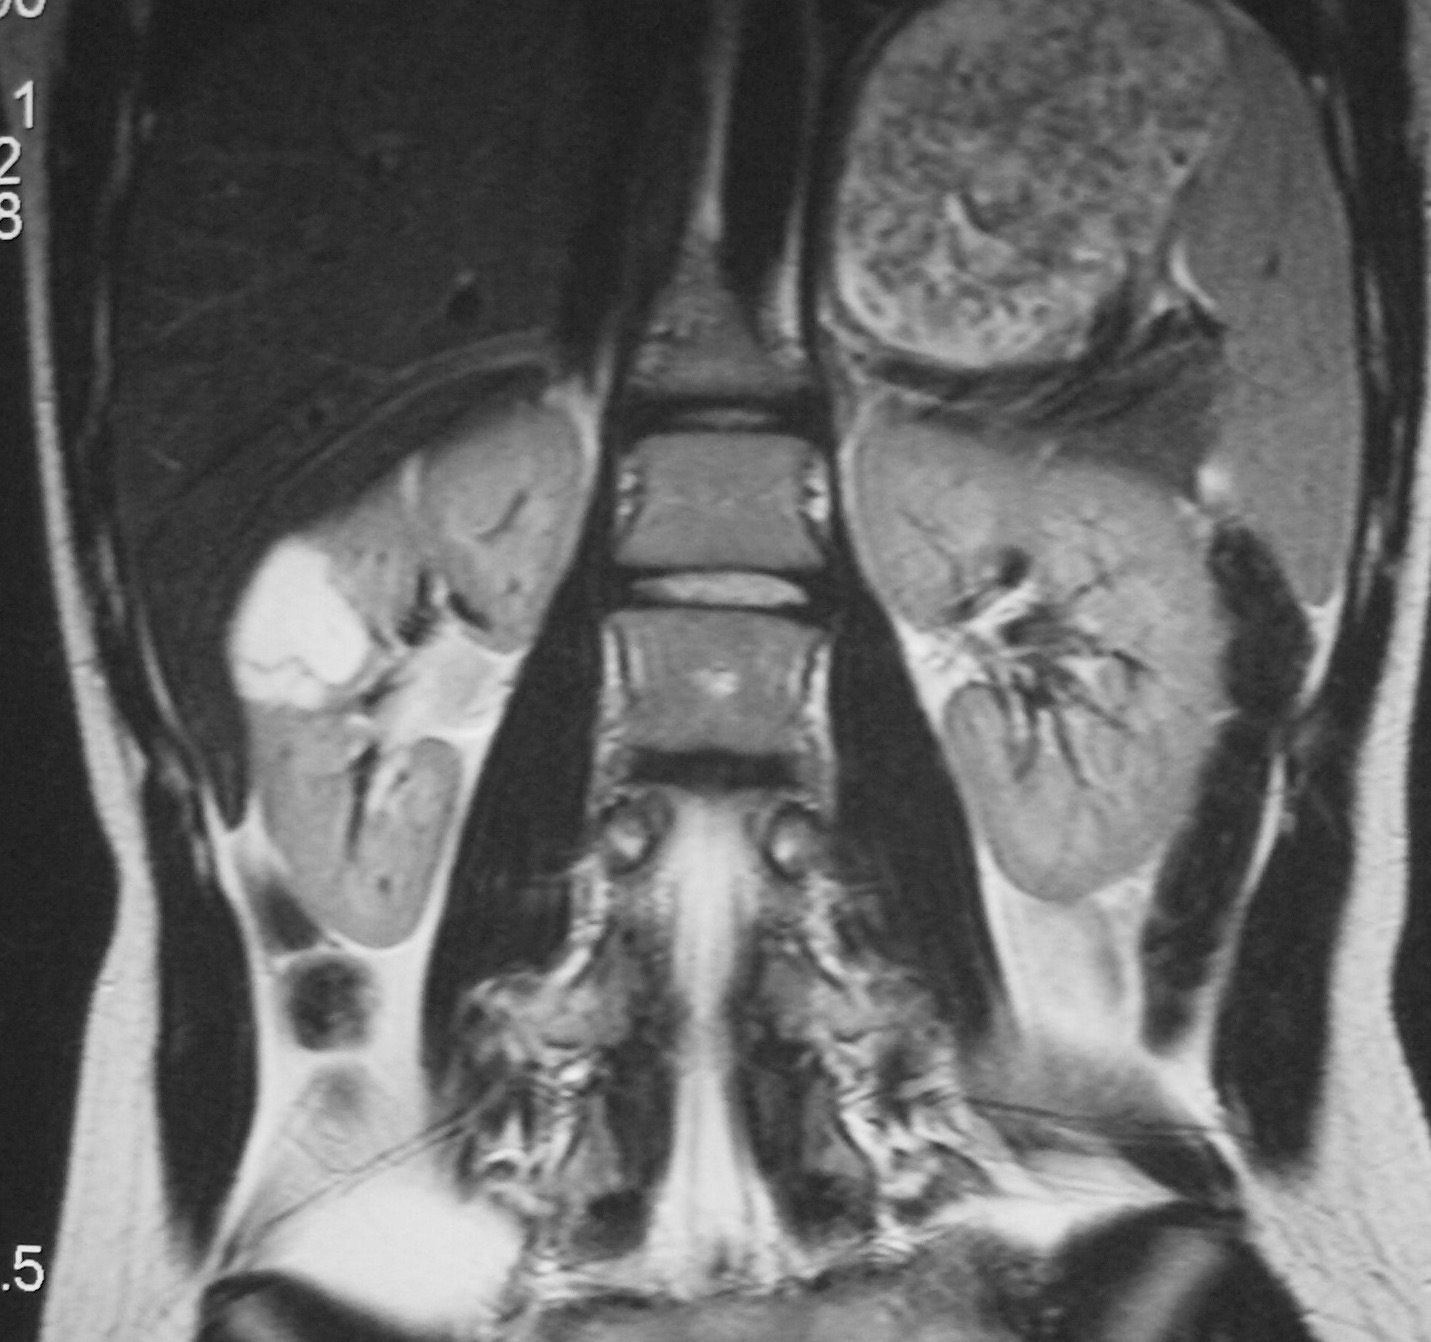

Fig. 10. Neuroblastoma intrarrenal. Niño de 9 años que presenta fiebre y dolor en la pierna izquierda. (A) Tomografía computarizada abdominal con contraste intravenoso. Masa intrarrenal sólida, con áreas necróticas, con mínimo parénquima circundante. (B) Resonancia magnética de control tras tratamiento con quimioterapia. Secuencia STIR. Cortes coronales de pelvis y ambas caderas. Lesiones hiperintensas en la medula ósea próxima a trocánter menor derecho, parte superior de hueso iliaco izquierdo y ambas regiones acetabulares.